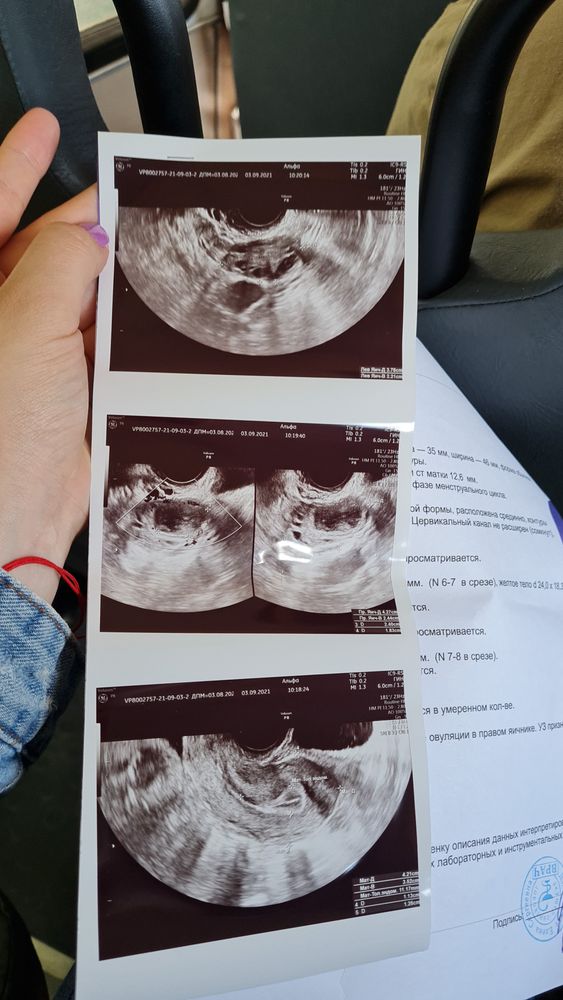

Значит и сейчас тоже пролет( хотя г по пышному эндометрию предположила Б

Люси Г, у вас по УЗИ эндометрий всего 11 мм - обычный для второй фазы. Беременный эндик на ранних сроках 17-20 мм. Непонятно теперь зачем Дюфастон 🤷♀️ А эти рекомендации вам даёт гинеколог или просто врач УЗИ?

У вас есть жёлтое тело в правом яичнике, значит овуляция была. Зачем дюфастон? Месячные придут через 14 дней примерно от овуляции, сами.